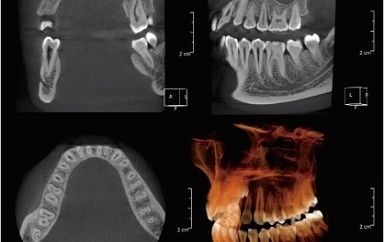

歯科用CT・セファロ(矯正用レントゲン)

今までのレントゲン撮影では、お口の中の様子は平面(2次元)でしか見られませんでした。

しかし、歯科用CTは、上下左右あらゆる角度から立体的にお口の中を観察できます。

レントゲンだけでは発見することができなかった病変や根管の形を確認しながら治療を進めます。